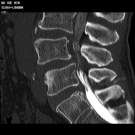

脊髓血管造影包括椎動脈、甲狀頸乾、肋頸乾、肋間動脈、腰動脈和髂內動脈等構成根髓動脈的動脈血管。頸段與上胸段脊髓動脈造影,可選用5~6F獵人頭Ⅰ型導管,Simmons導管或牧羊拐導管,Cobra導管,經股動脈穿刺,作椎動脈或鎖骨下動脈插管造影,即可顯示椎動脈、甲狀頸乾、肋頸乾。肋間動脈和腰動脈可選用4~5F,牧羊拐導管,強化Cobra導管或盤曲導管,在主動脈側壁和後側壁從下向上或從上向下,作小幅度滑動,逐條進行選插。第2~4肋間動脈平第5胸椎平面,第5~11肋間動脈依次降低一個椎體,開口於胸主動脈外側壁,上、下兩支動脈的間距約1~2mm。如尋找有困難,可將導管尖朝向主動脈側壁或後側壁注入8~10ml造影劑,觀察到肋間動脈或腰動脈開口後,再有目的地插入,只要插成功一支,其它的藉此依法類推。胸6以上肋間動脈開口比較靠近。腰動脈開口靠近腹主動脈後中線,兩側開口相距較近。

(2)肋間動脈和腰動脈:以1~3ml/s的流率,手推非離子型水溶性造影劑或60泛影葡胺4~8ml,以2張/s×3s,1張/2s×4s的程式攝正位片,必要時加側位片。